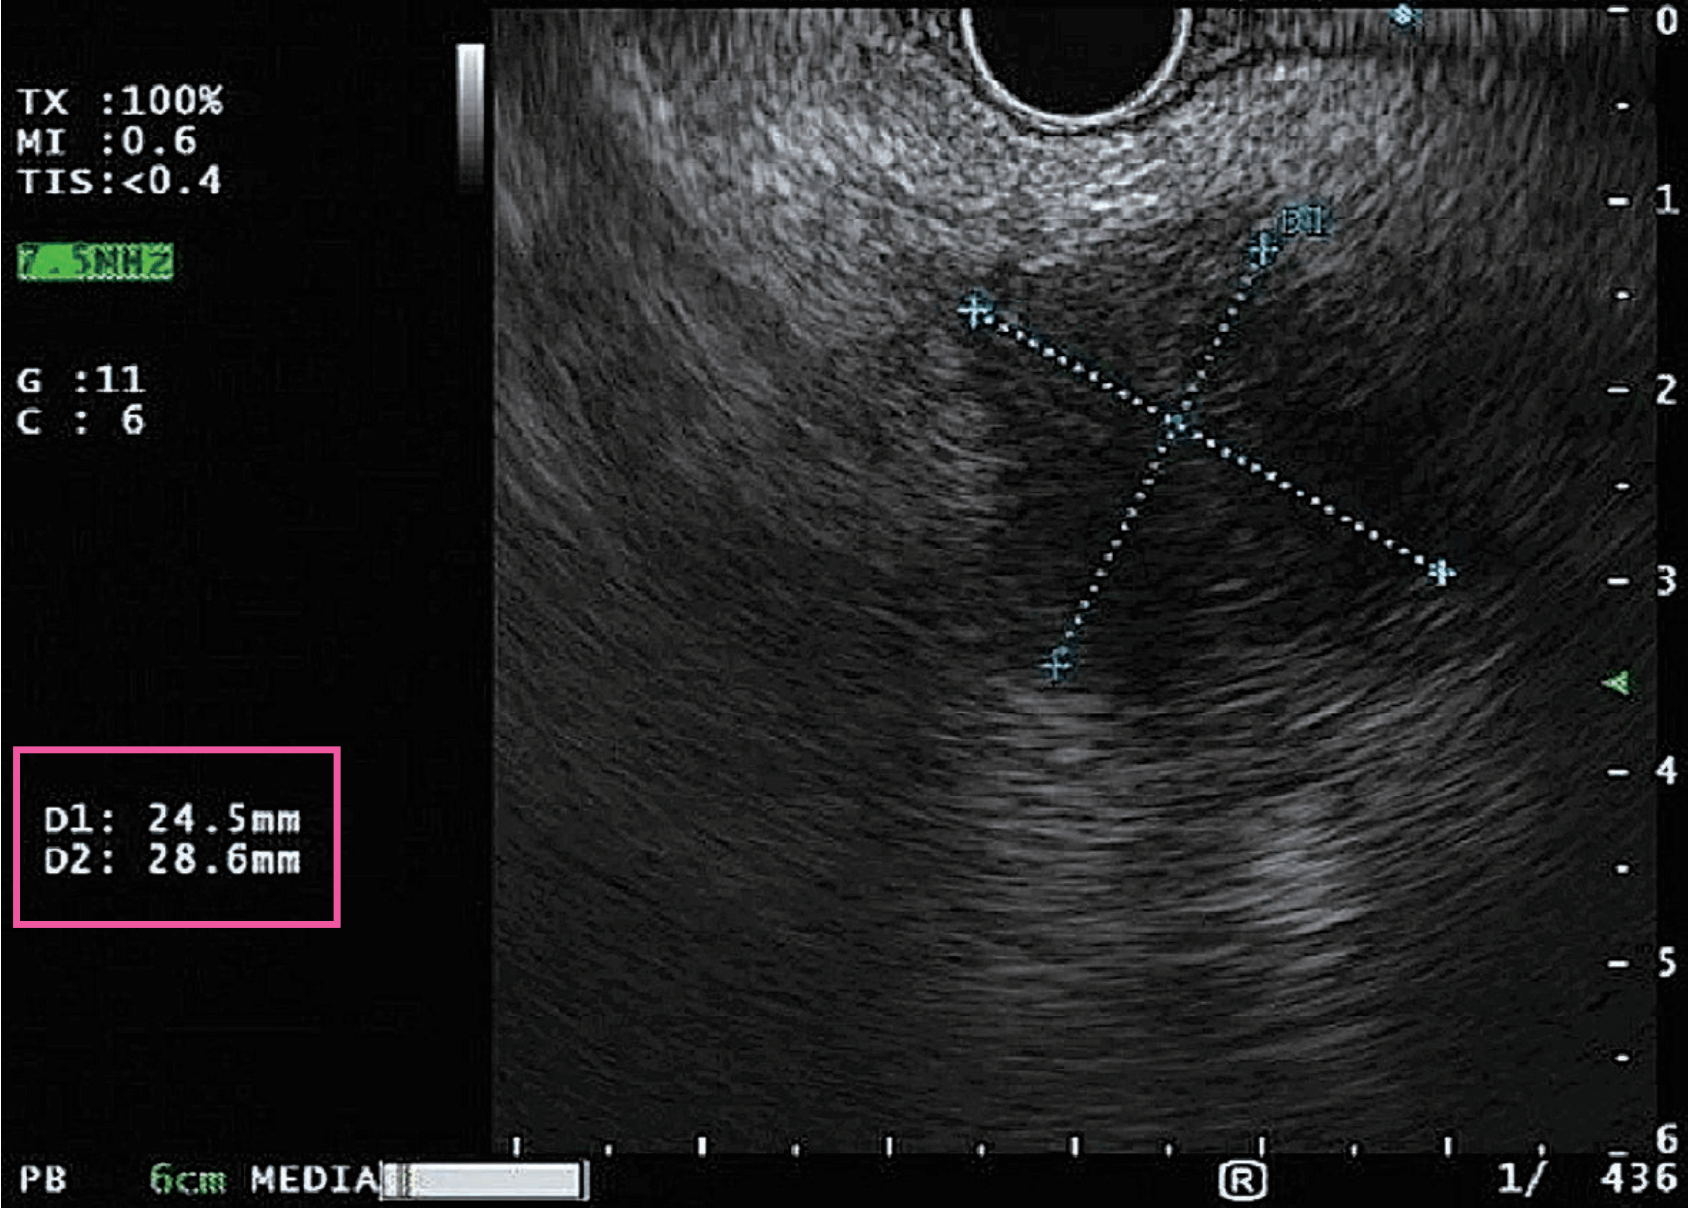

A 73-year-old male patient has hypertension, hyperlipidemia and painless obstructive jaundice. CT scan shows a pancreatic head/uncinate mass measuring 3.3 cm x 2.5 cm with biliary tree obstruction which was suspected to be malignant in nature. The mass is seen adjacent to the right hepatic artery. There are several hypodense nodules present in the right liver and caudate, most measuring around 1.4 cm x 1.2 cm and are likely metastases. Endoscopic Ultrasonography (EUS) and Fine Needle Aspirations (FNA) were performed using Olympus’s EU-ME2 PREMIER PLUS. A hypoechoic lesion measuring 2.9 cm x 2.5 cm was observed in the head of pancreas and was seen to be associated with a dilated common bile duct measuring 13 mm. Sludge was present in the distal CBD. The main pancreatic duct was not dilated (2 mm).

A hypoechoic lesion measuring 2.9 cm x 2.5 cm

A dilated common bile duct measuring 13 mm

A 43-year-old female patient has hypertension and autoimmune disease. She was diagnosed in 2013 with a gastric leiomyoma < 1 cm. EUS was performed again as part of a surveillance program. THE was used to view the gastrointestinal layers with less artifacts and more contrast. A 9.3 mm x10.4 mm homogenously hypoechoic ovoid lesion with discrete borders was seen from the mucosa to the muscularis propria.

A 9.3 mm x 10.4 mm homogenously hypoechoic ovoid lesion with discrete borders